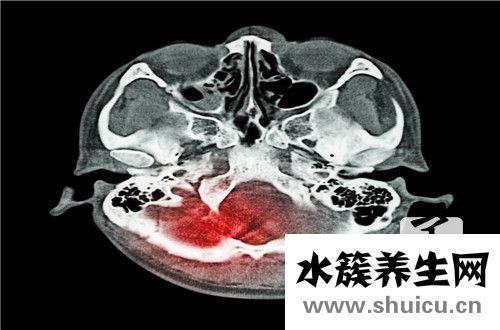

顱前窩骨折:可出現一側或兩側黑眼征(眼鏡征,熊貓眼),骨折線經過額篩竇時,常產生鼻出血 腦脊液鼻漏及嗅覺減退或喪失,或因氣體進入顱腔內產生外傷性顱內積氣; 其他征象 前額有皮膚損傷;結膜下淤血;單側或雙側視神經損傷癥狀 ;x線檢查骨折線經過框上壁 篩板 額竇和視神經管 顱腦ct發現前額腦挫裂傷或血腫等病變 額葉損傷癥狀;以及可能伴隨的眼 鼻部 顴弓附近損傷,眼球突出和活動受限

診斷要點是熊貓眼 腦脊液鼻漏 外傷后氣顱 ;x線顱底片發現骨折;ct顱底骨窗成像 或ct 3d成像發現前顱底骨折